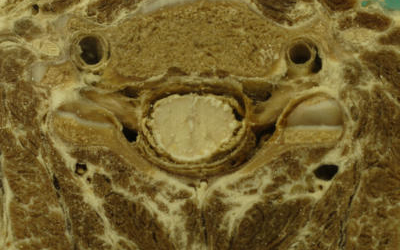

Gerincvelőből diagnosztizálható a szklerózis multiplex

A gerincvelő folyadékból kimutathatók a szklerózis multiplex korai jelei, ami segítheti a titokzatos betegség korai szűrését, diagnosztizálását - állapította meg egy új amerikai tanulmány, amelyről a R&D Magazine számol be. Bár a tanulmány kis méretű és biztosabbat csak további, nagyobb kutatás után tudnak mondani, az eredmények azt mutatják, hogy a betegség már korábban károsítja az idegrendszer bizonyos területeit, mint azt korábban gondolták.

A szklerózis multiplex olyan idegrendszeri betegség, amelynek tüneteként zsibbadás, járási nehézségek, látásproblémák léphetnek fel, s ezek hol erősebben, hogy gyengébben jelentkeznek. A betegségre vannak kezelési módszerek, gyógymód azonban nincs. Az orvosok előtt az SM oka ismeretlen, csupán annyit tudnak, hogy az idegsejteket borító mielin fokozatos csökkenése zavarokat okoz az agy és a gerincvelő által a szervezet többi részébe közvetített információk áramlásában. Ez okozza az említett tüneteket.

Mivel a korai jeleket az agyi képalkotó vizsgálatokkal nehéz észrevenni, ezért a betegség diagnosztizálására csak annak későbbi stádiumában kerül sor. Jelen kutatás keretében ezúttal a gerincvelő folyadék vizsgálatát használták fel kiindulási pontként.

Dr. Steven Schutzer, a tanulmány vezetője kilenc olyan páciens gerincvelő folyadékát elemezte, akiken a betegség korai tüneteit tapasztalták. Egy speciális nagy teljesítményű technológia segítségével fehérjék olyan csoportját fedezte fel, amellyel felismerhető volt az SM korai jele.

Amennyiben nagyobb létszámon végzett kutatások igazolják a mostani eredményt, a korai tünetekkel orvoshoz forduló pácienseket a gerincvelői folyadék gyors mintavételével lehetne szűrni a szklerózis multiplexet.